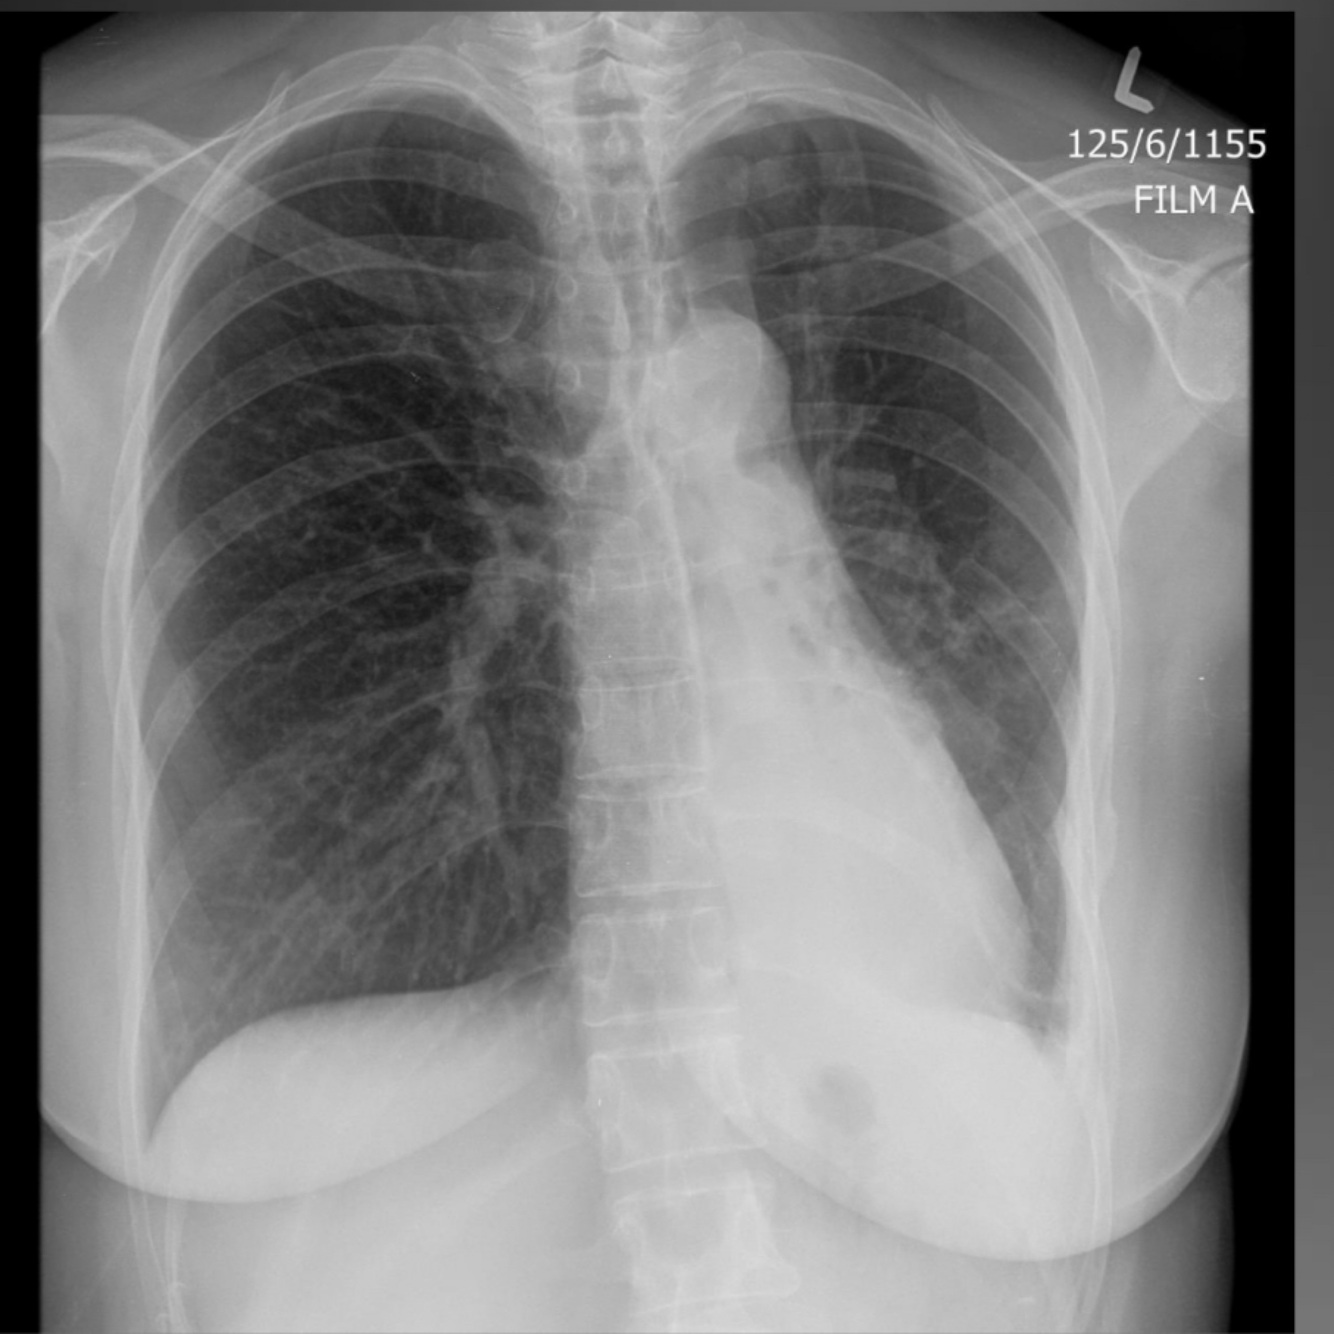

Q

Pleural effusion (tb infected)